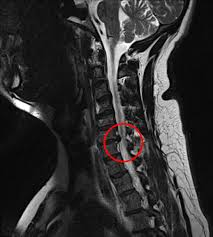

7 Wochen ein MRT der HWS mit der Diagnose Foraminastenose bds cervicaler Bandscheibenschaden Z.

Die Kernspintomographie ist für eine frühzeitige und verlässliche Diagnose von. Jahrelang wurde davon ausgegangen dass sich diese Veränderungen auf die weiße Gehirnsubstanz beschränken. Bei Zysten oder Vernarbungen im Bereich des Gehirns hindeuten. Wenn mehrere vernarbte Stellen größere Herde bilden spricht man von Plaques. Bei dem weißen Punkt rechts im Bild neben der Halswirbelsäule handelt es sich um eine Markierung auf der Haut die den Schmerzpunkt anzeigt. Es handelt sich um eine Schnittbild im coronaren Strahlengang parallel zur Stirn Der weisse Fleck ist ein Anschnitt der Aorta die dort einen Bogen macht. Ich weiß aber wie quälend es ist solange auf die Befundbesprechung zu warten. Ist die Aufnahme von vorne oder von hinten. Die Kernspintomographie ist für eine frühzeitige und verlässliche Diagnose von.

Bei Zysten oder Vernarbungen im Bereich des Gehirns hindeuten. Zur weiteren Differenzierung zwischen den Ursachen der Flecken sind Tests erforderlich die in der Regel durch einen Neurologen durchgeführt werden. Das Rückenmark als Schlüssel zur MS-Diagnostik. MRT der LWS T2 linkes Bild Weiß kann man die Entzündung der Lendenwirbelsäule erkennen da die Bandscheibe durch die Fehlstellung aufgebraucht wurde und nun Knochen auf Knochen reibt und eine Entzündung des Knochens entsteht. Ich habe viele mrt bilder von mir daheim. 7 Wochen ein MRT der HWS mit der Diagnose Foraminastenose bds cervicaler Bandscheibenschaden Z. Ein Computer wandelt diese Signalen in sichtbare Bilder um.